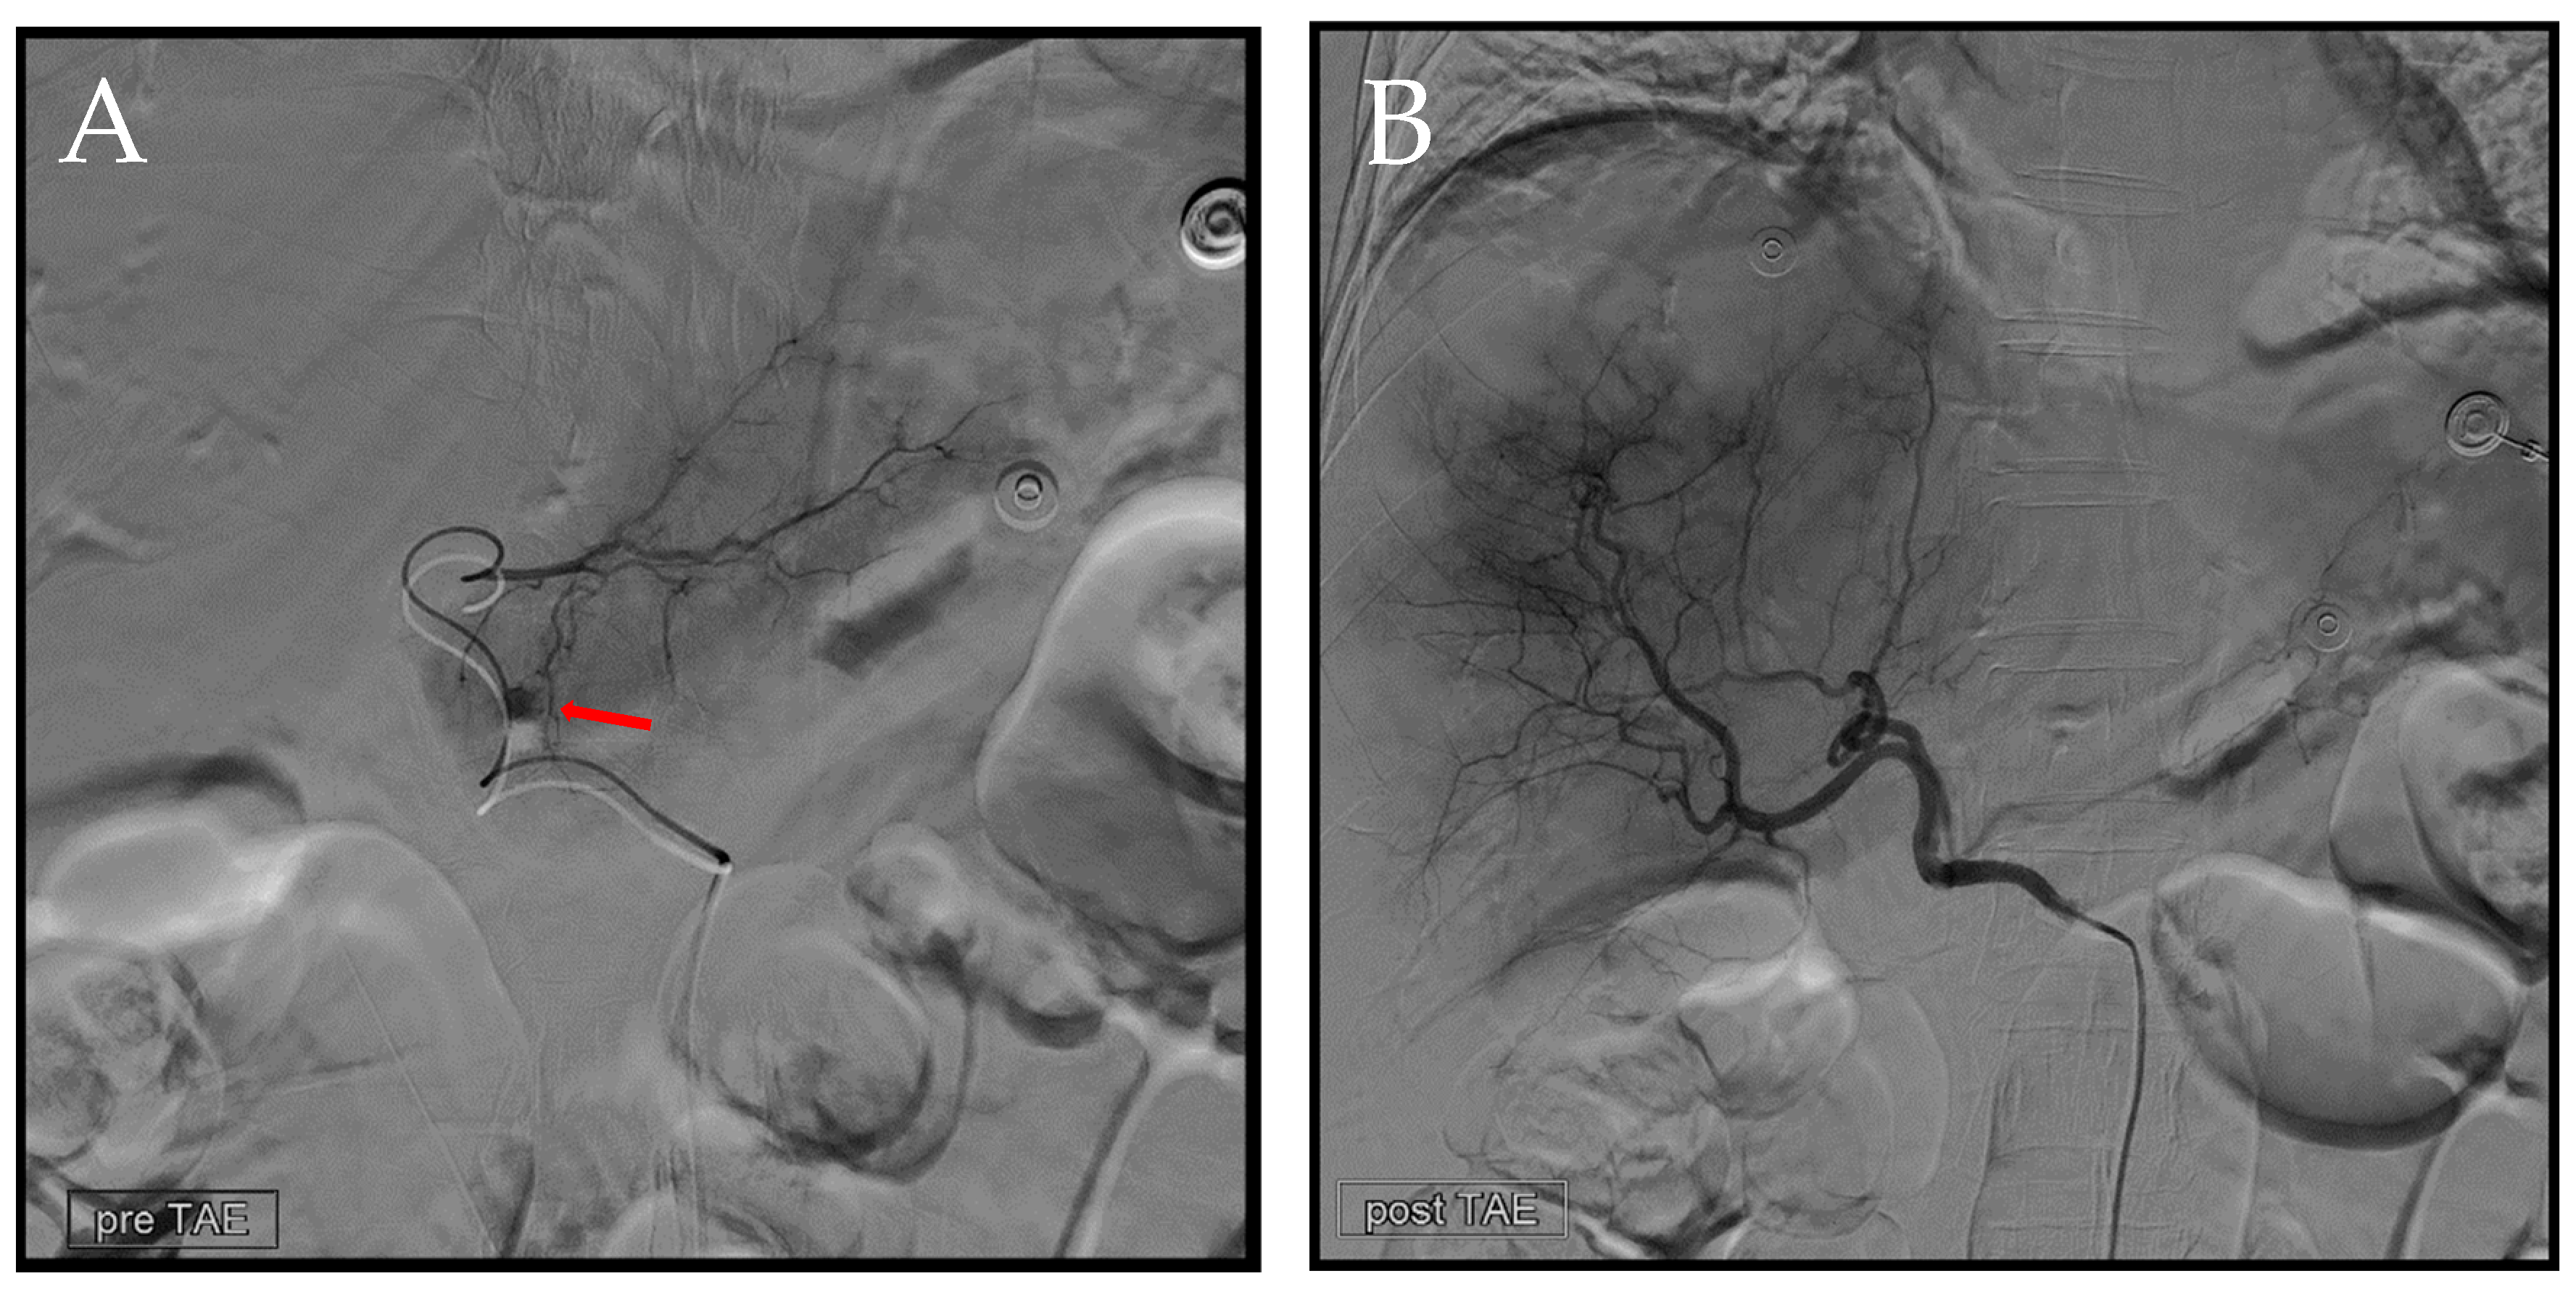

Figure 7. Second TAE. (A) Utilizing a 1.98Fr. Asahi microcatheter, access was established into a branch of the left hepatic artery. Subsequent angiography was performed to precisely identify the location of the extravasation (arrow). Following this, embolization was carried out using EG gel of a similar size to that used in the previous procedure. (B) Post-embolization, we conducted another angiography at the celiac trunk to confirm the absence of any additional extravasation.